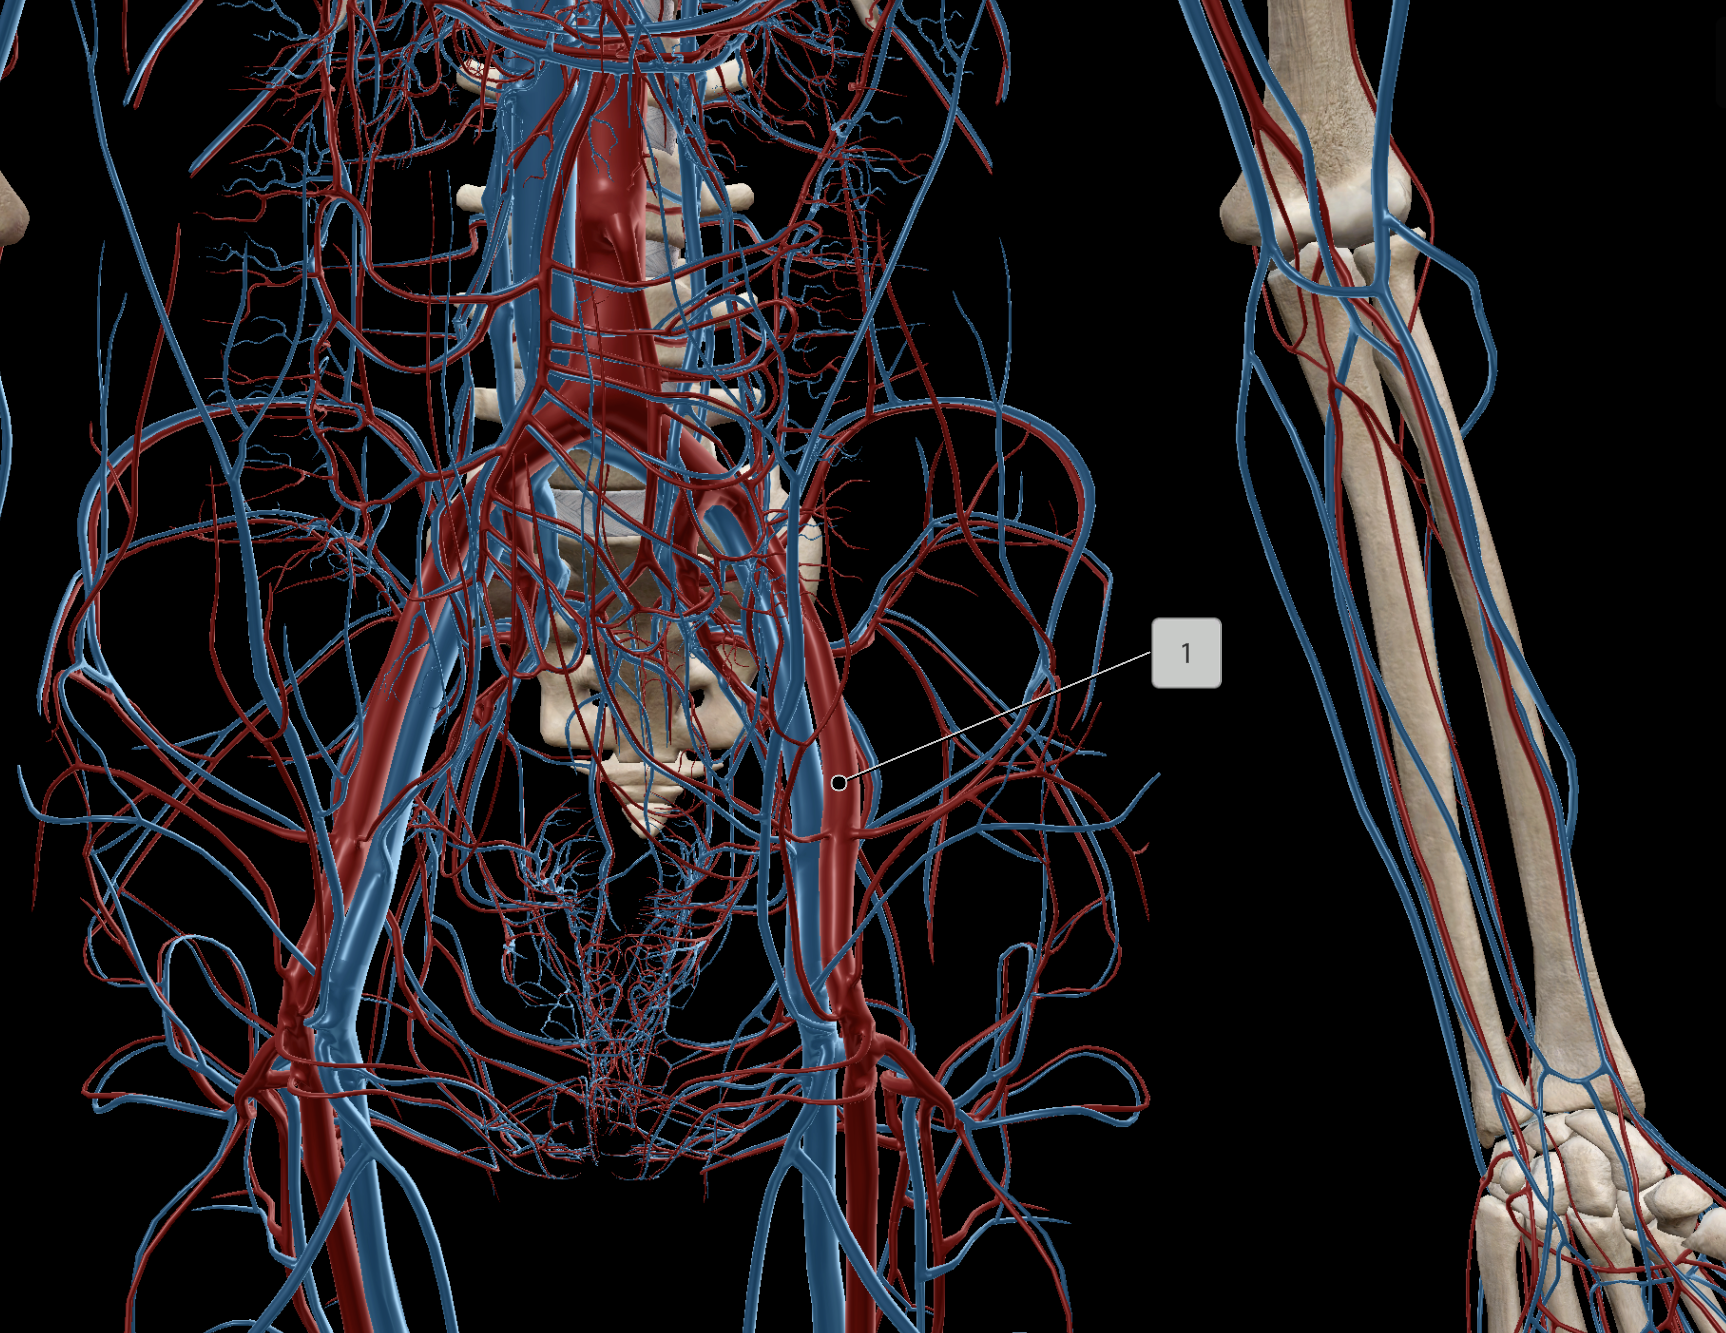

Inferior Vena Cava

Common Iliac Artery

Internal Iliac Artery

External Iliac Artery

Inferior Mesenteric Artery

Abdominal Aorta

Superior Mesenteric Artery

Common Iliac Vein

External Iliac Vein

Internal Iliac Vein